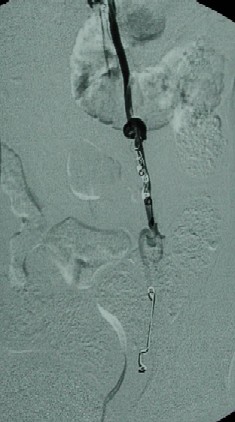

Image Guided Transcatheter Embolization

Images (on the left): 1st image is a venogram      obtained with left testicular vein catheterization during the embolization procedure. 2nd image is a post-embolization image demonstrating multiple small metal spring coils in the vein. Additionally, sotredecol was used to close the vein more effectively in this case.